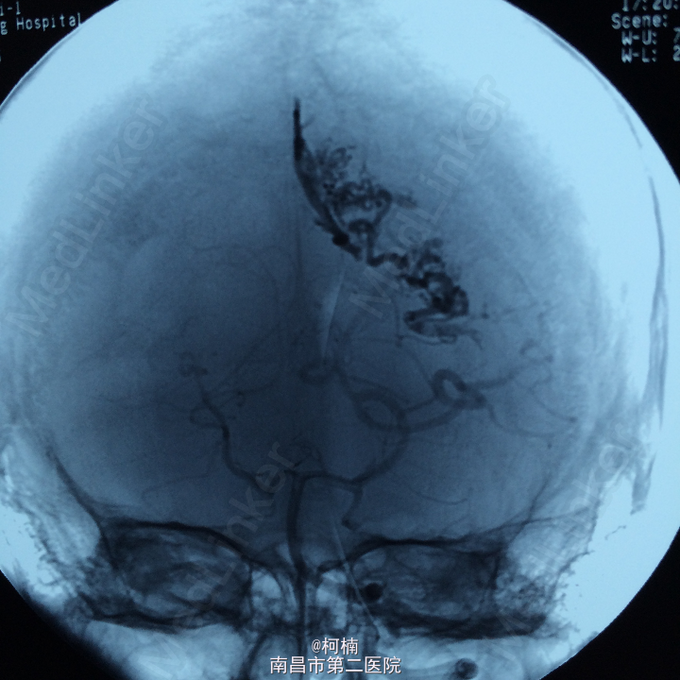

诊断:脑动静脉畸形 处理:予急诊行DSA检查,提示脑动静脉畸形,予行血管内栓栓塞治疗